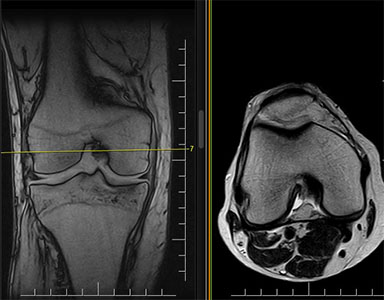

Grazie alle diverse pesature di immagine che possono essere ottenute tramite una scansione RM, si apprezzano, per esempio, a livello lombare ernie/protusioni discali, schiacciamenti vertebrali, crolli, o sofferenze dell’osso intraspongioso; a livello invece osteoarticolare si riesce ad evidenziare con grande precisione i legamenti e i tessuti muscolari che compongono l’articolazione oggetto di studio e quindi, le eventuali patologie correlate a queste, come ad esempio artrosi, lesioni legamentose e muscolari, osteocondropatie.

risonanza magnetica al ginocchio